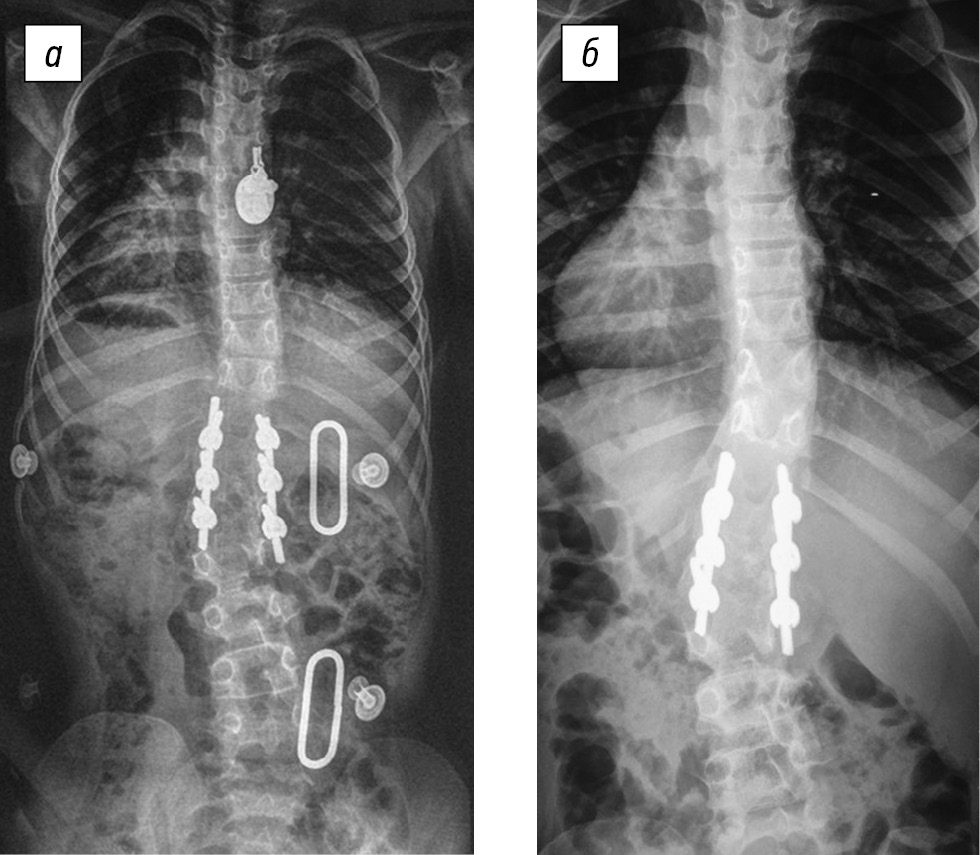

Клиническое наблюдение. Ребенок В., 6 лет, с врожденным кифосколиозом на фоне заднебокового полупозвонка L2, через 5 дней после оперативного лечения снабжен функционально-корригирующим корсетом на туловище. На рентгенограммах позвоночного столба до операции (рис. 4) заднебоковой полупозвонок на уровне L2 с углами деформации, поясничная левосторонняя локальная сколиотическая дуга на уровне полупозвонка — 36°, правосторонняя компенсаторная грудная дуга — 30°. Величина локального кифоза — 23° по Cobb. Величина грудного кифоза — 51° по Cobb.

На рентгенограммах после оперативного лечения отмечалась радикальная коррекция локальной врожденной деформации позвоночника грудного отдела, положение металлоконструкции правильное, стабильное. Правосторонняя компенсаторная сколиотическая противодуга на уровне позвонков Th11–Th7 величиной 18°.

Результаты ортезирования демонстрирует рис. 5. На рентгенограммах через 6 мес. в функционально-корригирующем корсете положение металлоконструкции в грудном отделе стабильное, произошла коррекция правосторонней компенсаторной противодуги на уровне позвонков Th11–Th7 до величины 6°.

На рентгенограммах через 12 мес. без корсета положение металлоконструкции в грудном отделе стабильное. Потери достигнутой коррекции деформации по сравнению с периодом ортезирования в 6 мес. нет: правосторонняя сколиотическая дуга Th11–Th7 величиной 10° по Соbb. У данного пациента в ходе хирургического вмешательства удалось полностью исправить локальную врожденную дугу деформации, зафиксировав минимальное количество позвоночно-двигательных сегментов и уменьшить величину компенсаторной противодуги. Использование после операции функционально-корригирующего ортеза позволило не только добиться стабилизации компенсаторной дуги противоискривления, но и осуществить коррекцию ее величины. Ребенок до настоящего времени пользуется корсетом и будет находиться под активным наблюдением с периодичностью раз в 3 мес. до завершения периода костного роста.

Рис. 4. Рентгенограммы позвоночника в двух проекциях пациентки В., 6 лет. Врожденный кифосколиоз на фоне заднебокового полупозвонка L2, после оперативного лечения

Рис. 5. Рентгенограммы позвоночника пациентки В., 6 лет. Врожденный кифосколиоз на фоне заднебокового полупозвонка L2: а — через 6 мес. в функционально-корригирующем корсете; б — через 12 мес. в положении стоя без корсета